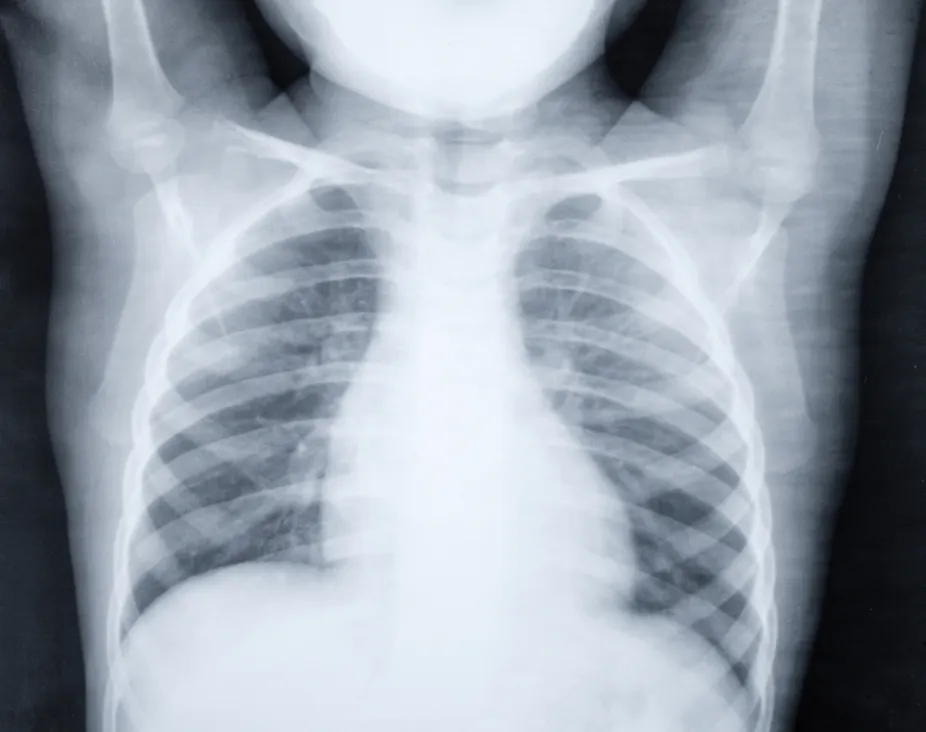

Bronchopneumonia Wikipedia

Pneumonia Wikipedia